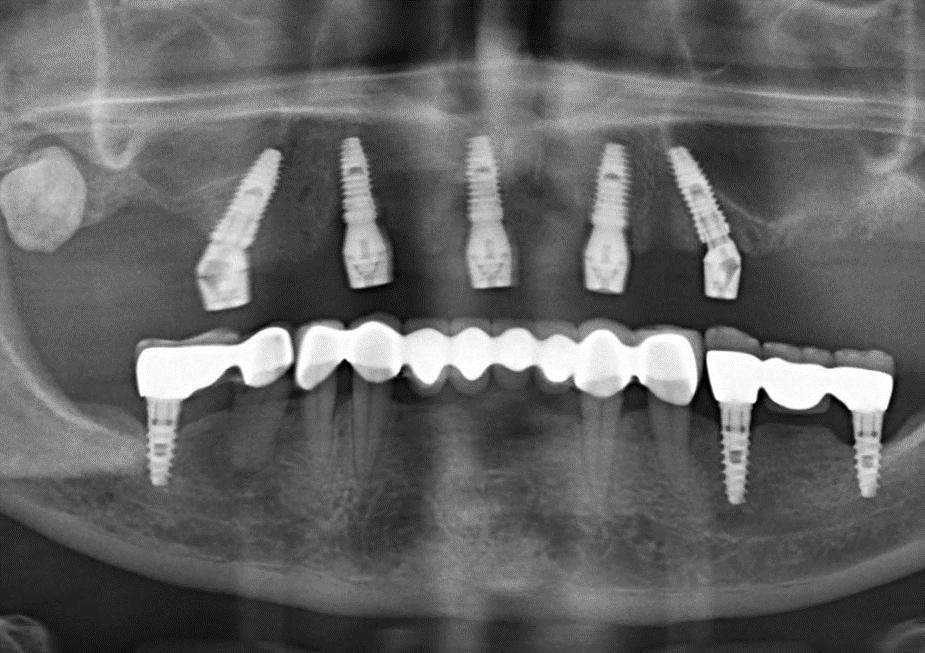

Cerrahi & Protez

• Kılavuzlu yerleştirme

• Post-op kontrol

• İmplant pozisyonlarının kemik içerisindeki pozisyonunun belirlenebilmesi için hastaya ait konik ışınlı bilgisayarlı tomografi (CBCT) görüntüsü DICOM formatında iletilmelidir. Görüntüleme merkezine hasta dosyasını hangi formatta istediğinizi lütfen belirtin.